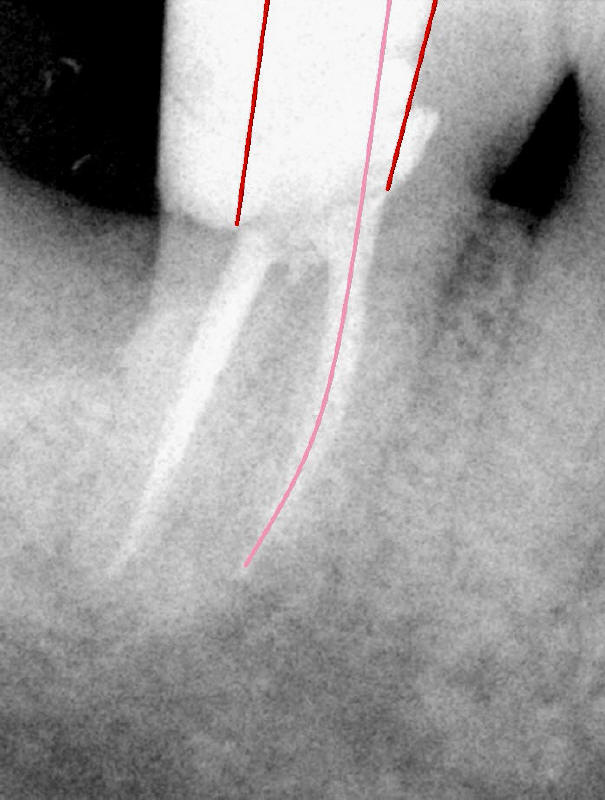

In fact, there is a separated file in the mesial canal (Fig.2: S). The related problem is that the mesial portion of the pulpal roof is not removed (arrowheads). The access to the pulp is limited (Fig.3: red lines), particularly to the mesial canal. The file must have been bent twice (pink line in an S shape) before separation. By comparison, the access to the pulp of another lower 2nd molar is sufficient (Fig.4 red lines) and the file is bent only once (pink line).